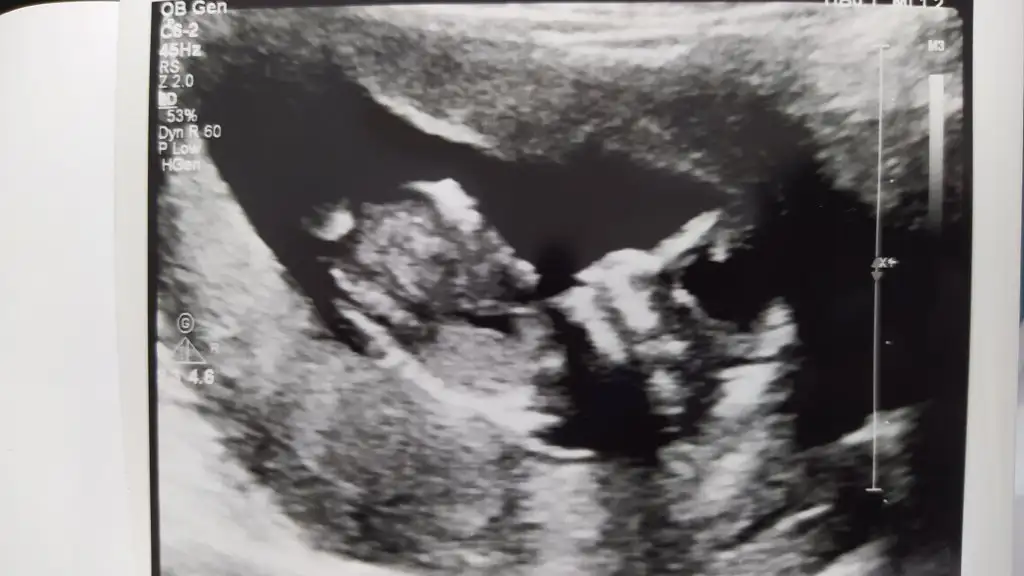

Karındansa kız vajinalse erkekBana da bir yorum yapar mısınız![]()

Ultrason resimleriniz varmı?? Ordan tahmin edebilirim

Banada yorum yaparmisinizUltrason resimleriniz varmı?? Ordan tahmin edebilirim